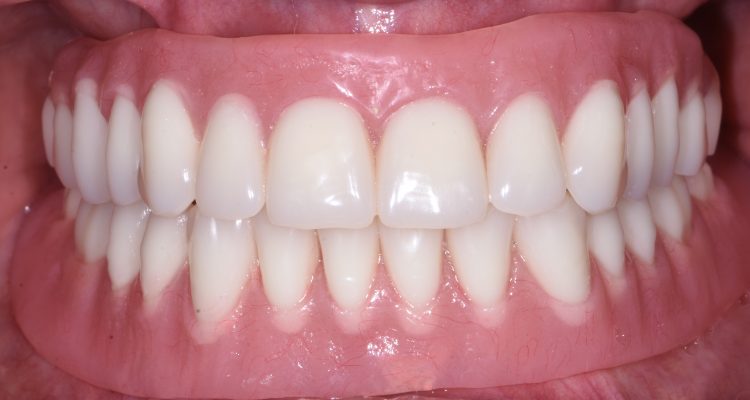

Once the implant has been fully integrated with the bone, the next phase begins: the fabrication and placement of your permanent artificial tooth or teeth. This typically requires two to four appointments and combines the technical and artistic aspects of prosthodontics. Dr. Leong uses advanced technology and his expertise in dental aesthetics to create lifelike, durable restorations that blend seamlessly with your natural smile.

Once your final dental prosthetics are attached, you’ll be able to eat, speak, and smile confidently, just like you did with your original teeth.